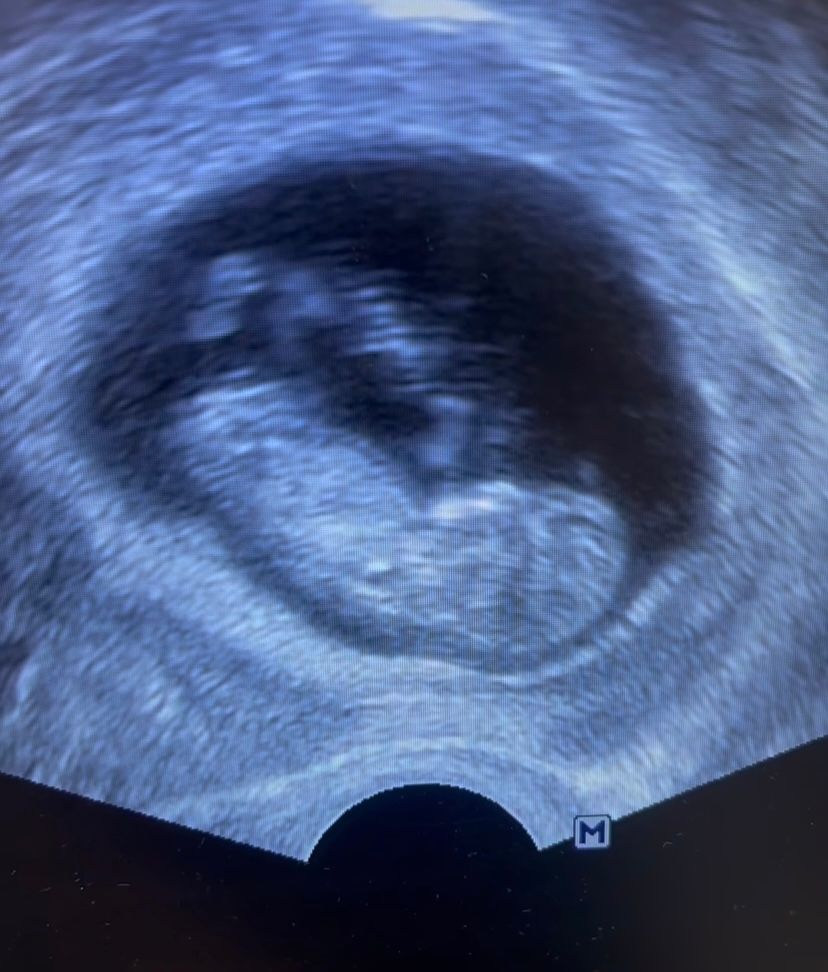

Тут нашему долгожданному крохе 11 недель. Ждали 9 лет. Первая беременность после 3-ого переноса

Тут ктр 33 мм. Малышу не нравилось узи и он очень активно двигался и махал руками и ногами. Ждем 1скрининг 26 июля. Очень переживаю, так как боюсь за кроху ведь ниразу в жизни не было беременности и не было найдено причин бесплодия ,вдруг эти скрытые причины повлияют на малыша и беременность.3-ий перенос был на згт и первый удачный,до этого в ец и не было даже прикрепления. Каждый день или через день слушаю сб доплером…и не могу поверить что он у меня там…